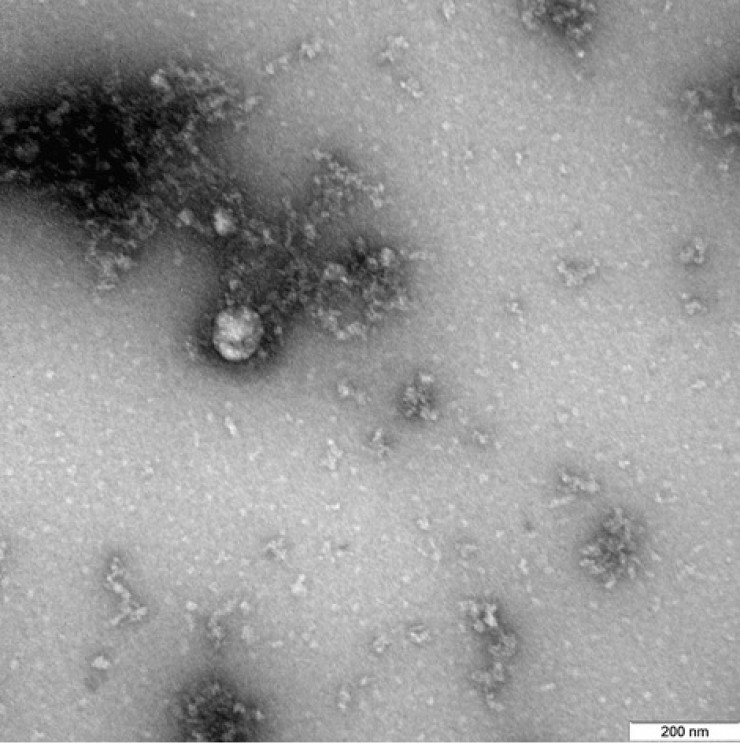

Ученые Роспотребнадзора впервые сфотографировали под микроскопом "британский" штамм коронавируса. Как сообщается на сайте ведомства, "британский" штамм коронавируса был выделен от пациента в декабре 2020 года, передает Tengrinews.kz.

"Фотография вируса под микроскопом получена в рамках продолжающегося изучения свойств данного варианта нового коронавируса, включая его структурные особенности и проявления в клеточных культурах и экспериментальных моделях с использованием лабораторных животных", - говорится в сообщении.

Фото: rospotrebnadzor.ru